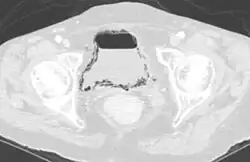

| Emphysematous cystitis in computertomography | |

Diagnosis is made by patient history of passing air or a sputtering urine stream. CT scans may show air in the urinary bladder or bladder walls.